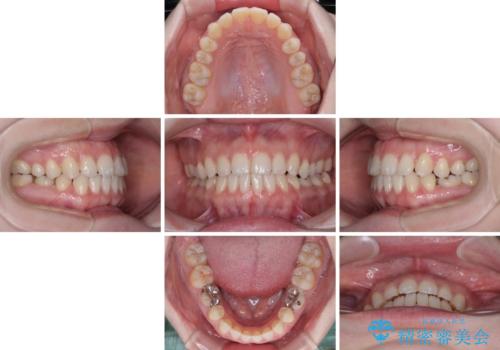

すきっ歯をインビザラインできれいな歯並びに改善

- 前歯の隙間を気にして来院された患者様です。

隙間や叢生の程度はそれほど著しいものではなかったので、インビザラインでもワイヤー矯正でも対応可能でしたが、極力目立たない装置を希望されたため、インビザラインにて矯正治療を行うこととしました。

すきっ歯の原因は色々ありますが、嚥下や発音時の舌突出癖が大きな原因となることがあります。

こちらの患者様も強い突出癖があったため、舌のトレーニング指導を行いました。